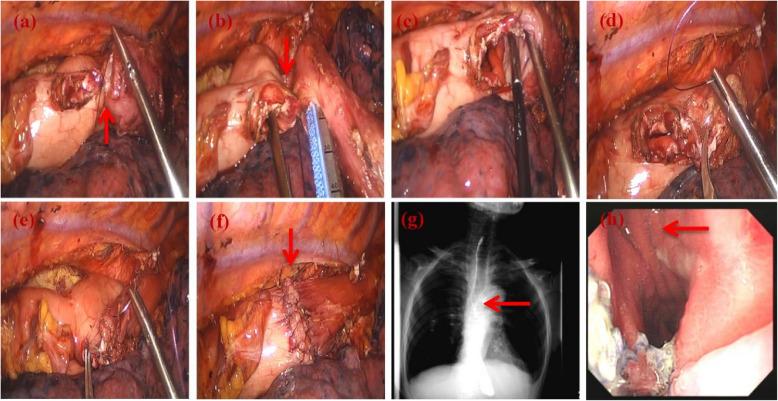

Cancers of the lower esophagus and esophagogastric junction (EGJ) are highly aggressive and have poor prognoses. Minimally invasive Ivor-Lewis surgery (MIIL) is the preferred treatment, but anastomotic leakage (AL) remains a critical complication of this procedure. In the present study, we introduce a novel double-layered scallop-shaped anastomosis (DLSSA) technique and compare its outcomes with those of circular stapled esophagogastric anastomosis (CSEA).

食管下段癌和食管胃交界部(EGJ)癌具有高度侵袭性,预后较差。微创Ivor-Lewis手术(MIIL)是首选治疗方法,但吻合口漏(AL)仍然是该手术的关键并发症。在本研究中,我们介绍了一种新型双层扇形吻合术(DLSSA)技术,并将其结果与圆形吻合器食管胃吻合术(CSEA)的结果进行比较。